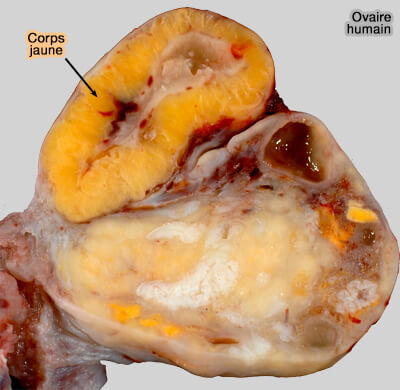

Reproduction : développement folliculaire terminal

Cycle ovarien : phase lutéale (corps jaune de gestation)

Corps jaune de gestation

Lors de fécondation, le corps jaune persiste :

(Photo : Ed Uthman)

- soit jusqu'à ce que le placenta prenne le relais dans certaines espèces dites " espèces placenta dépendant " comme la chatte ou la femme.

- soit pendant toute la durée de la gestation dans certaines espèces dites " espèces corps jaune dépendant " comme la chienne,